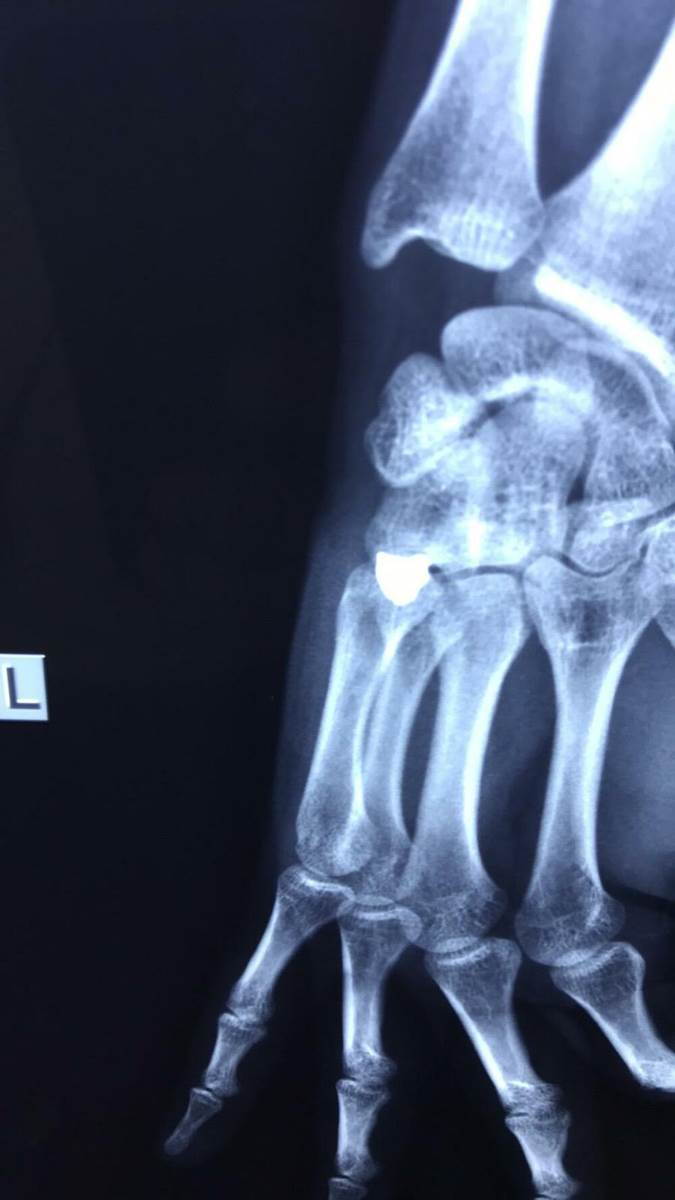

POGLEDAJTE FOTOGRAFIJE RENDGENSKOG SNIMKA! Ovo je metak koji je izvađen iz šake srpskog mladića (FOTO)